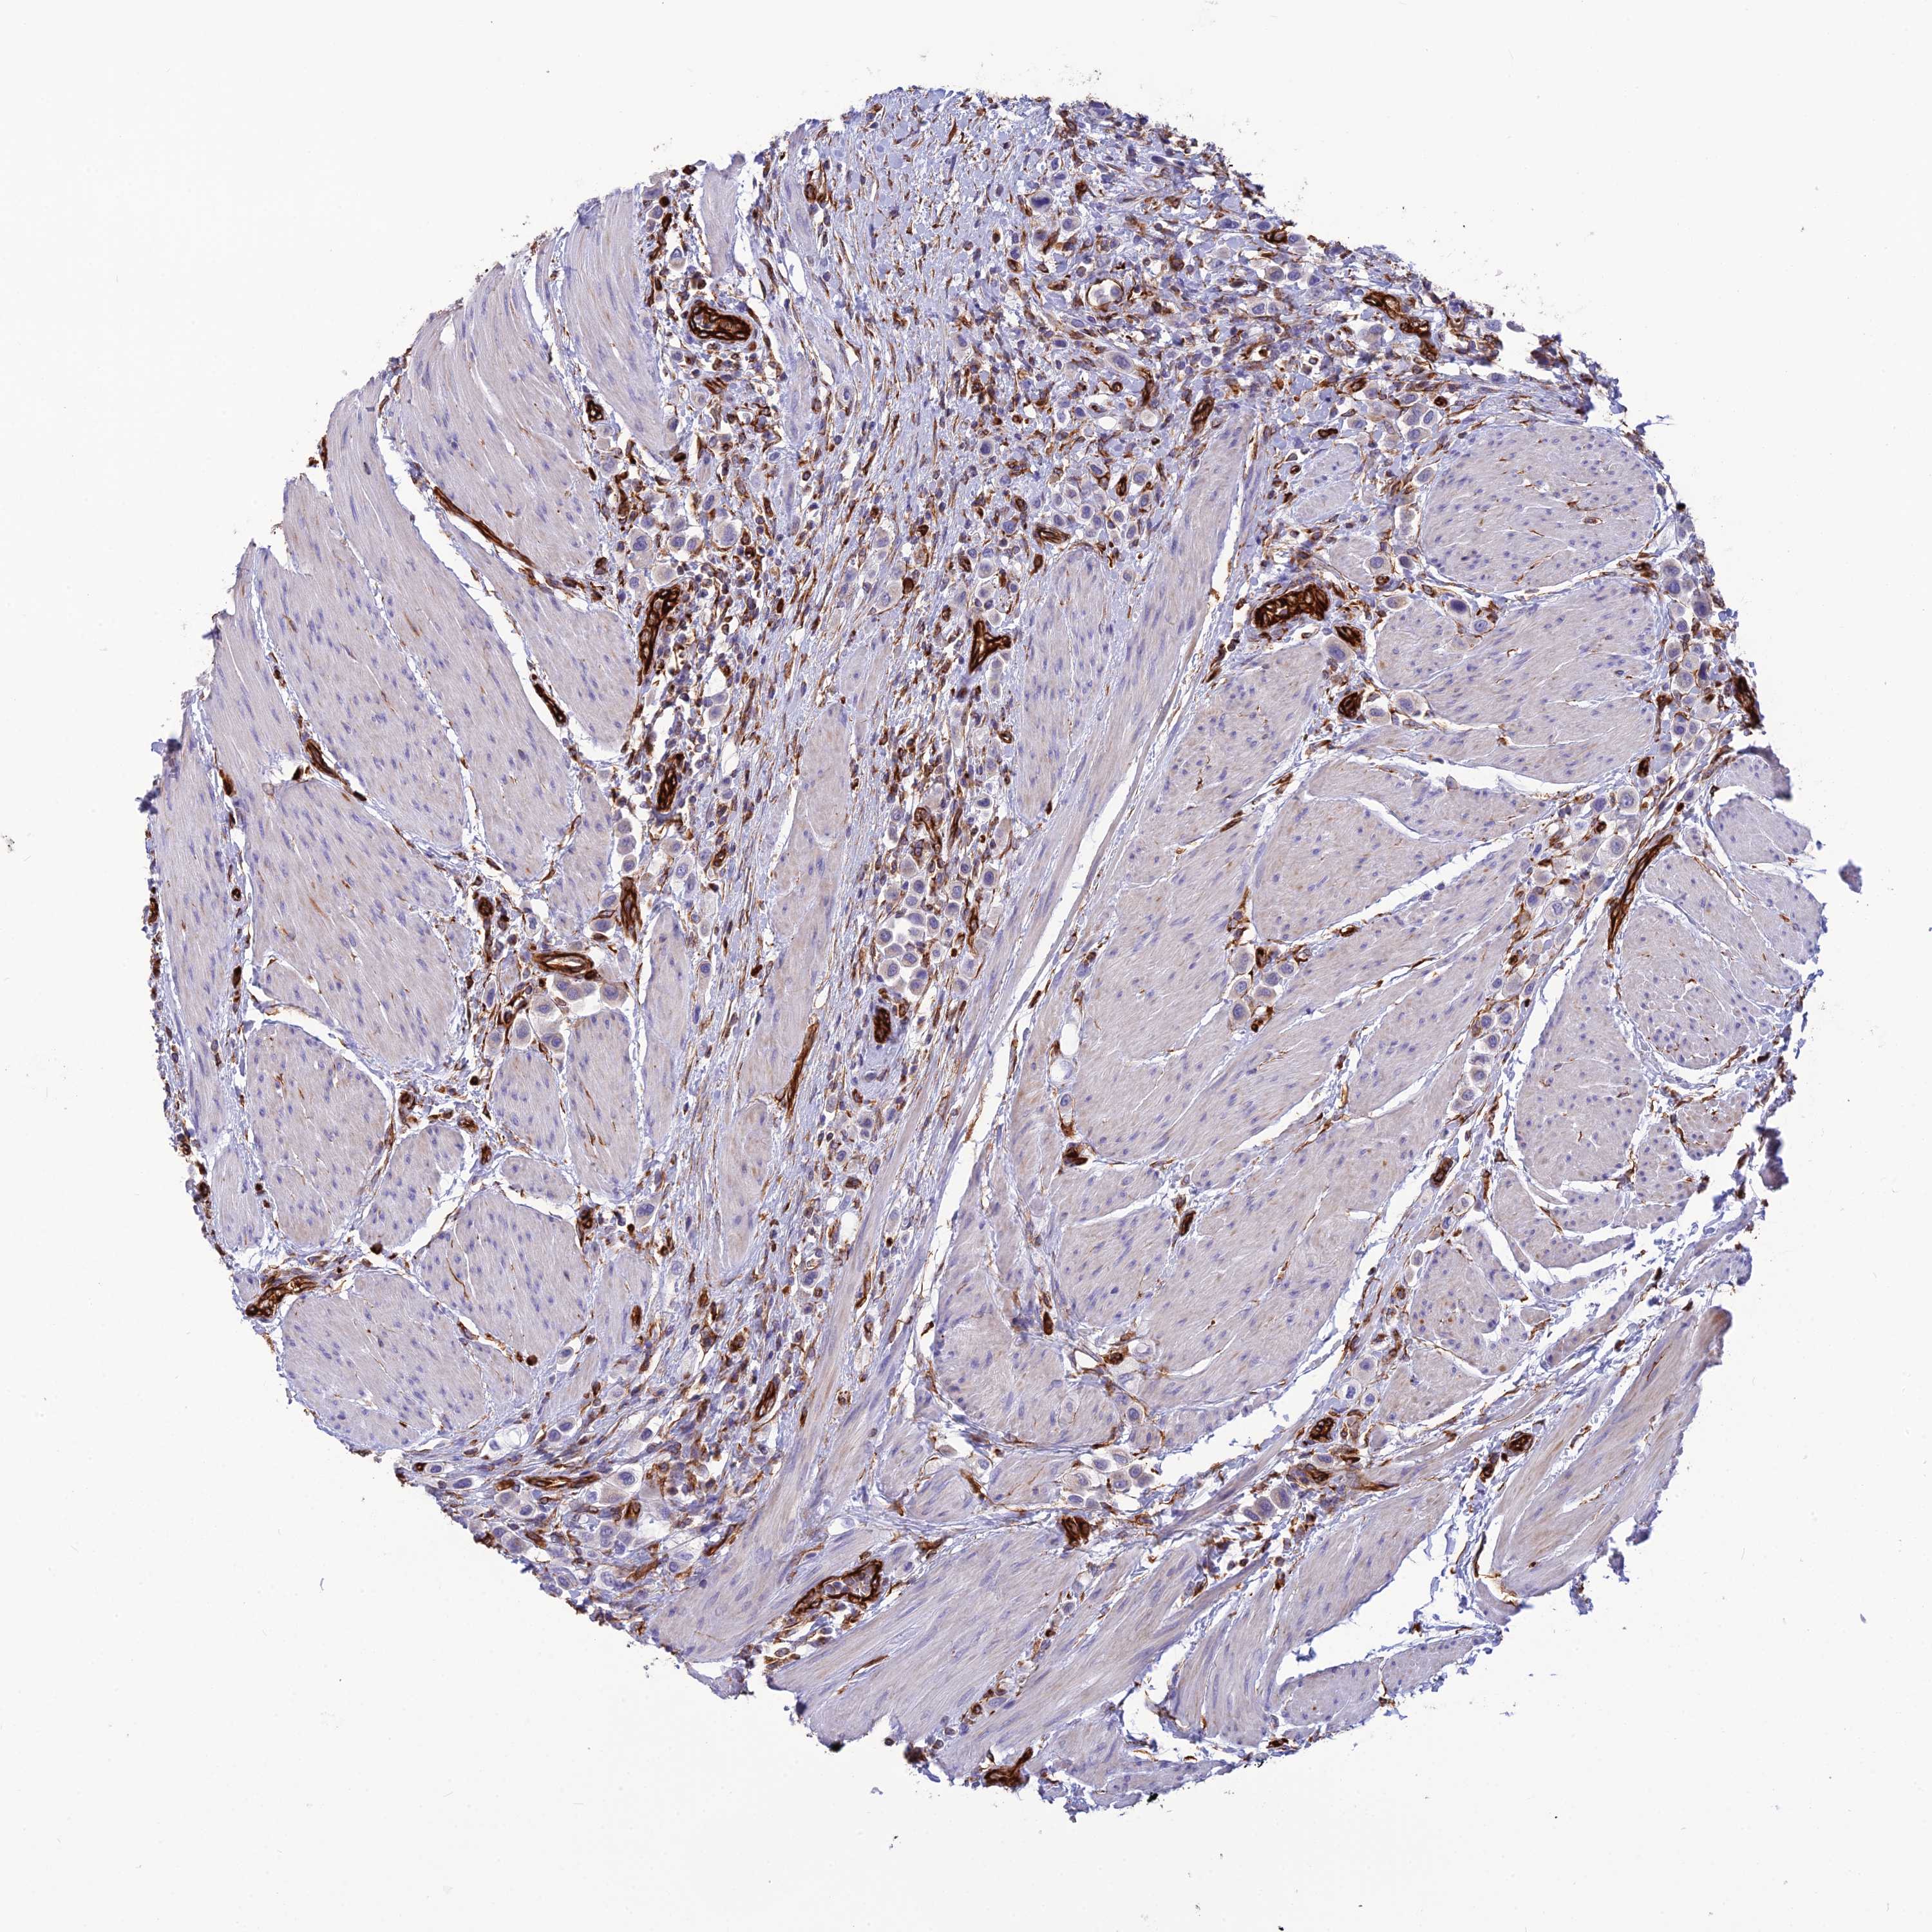

UROTHELIAL CANCER - Protein expressioni

A mouse-over function shows sample information and annotation data. Click on an image to view it in a full screen mode. Samples can be filtered based on level of antibody staining by selecting one or several of the following categories: high, medium, low and not detected. The assay and annotation is described here.

Note that samples used for immunohistochemistry by the Human Protein Atlas do not correspond to samples in the TCGA dataset.

Antibody stainingi

Antibody staining in the annotated cell types in the current human tissue is reported as not detected, low, medium, or high, based on conventional immunohistochemistry profiling in selected tissues. This score is based on the combination of the staining intensity and fraction of stained cells.

Each image is clickable and will lead to virtual microscopy that enables deeper exploration of all samples and also displays staining intensity scores, fraction scores and subcellular localization as well as patient and tissue information for each sample.

Antibody HPA044748

Antibody HPA050397

Urothelial carcinoma, High grade

Urothelial carcinoma, Low grade